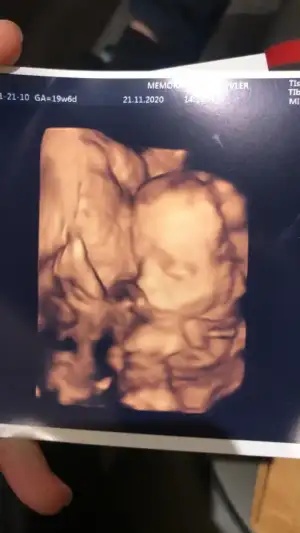

Kızlar dün kontrol amaçlı gitmiştim doktora bende biliyorsunuz benim bebeğim de ayaklarını kafasına vurup duruyordu nasıl duygulandım ama hareket ettikçe 😢😢😢

Eklentiler

• AB2CDB88-8607-475D-B429-AC86D5AF7654.webp

AB2CDB88-8607-475D-B429-AC86D5AF7654.webp

19,8 KB · Görüntüleme: 88

• 20921000-DF58-4381-BB50-587EFCE4B5DA.webp

20921000-DF58-4381-BB50-587EFCE4B5DA.webp

19,6 KB · Görüntüleme: 93

masallah 🧿 ay oglum aklima geldi oda 4 aydan sonra ayaklar hep havada suratindaydi böyle ve birdahada indirmedi ayaklarinii ayni bu sekildede dogdu ikiye katlanmis gibi 🤭doktorlar sezeryanda cok gülmüstü